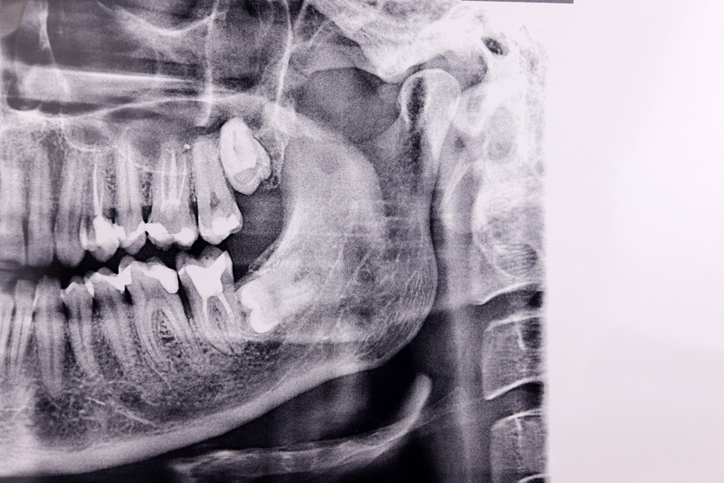

1. 진단: 엑스레이로 사랑니 위치, 뿌리 모양, 신경관과의 거리 확인

1. 턱 안쪽 신경과 가까운 경우 → 대학병원급에서 CT 촬영 후 수술